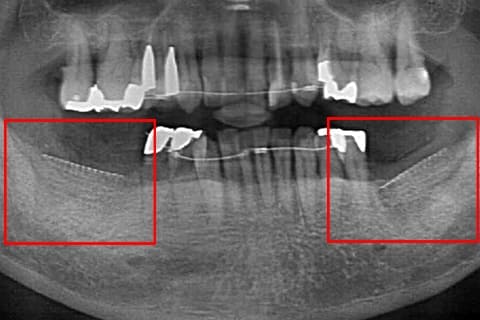

CASE.02 「GBR・骨誘導再生法」

-

- 治療内容

- GBR・骨誘導再生法

- 治療費用

- ¥110,000